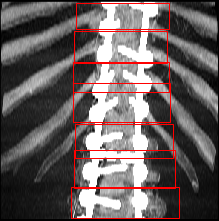

SINAPSIS’ technological development will be transversal, that is, applicable to different surgical scenarios, including spinal interventions, biopsies, stereo electro-encephalography (used on cases of drug-resistant epilepsies), deep brain stimulation, ventriculoscopies, ablations and arthroscopies.

Vicomtech’s role in the SINAPSIS project is focused on the development of new algorithms for intelligent surgical planning and machine learning applied for medical image processing. Developments will be validated on the surgical scenarios of stereo-electroencephalography (SEEG) and lumbar vertebral fusion.